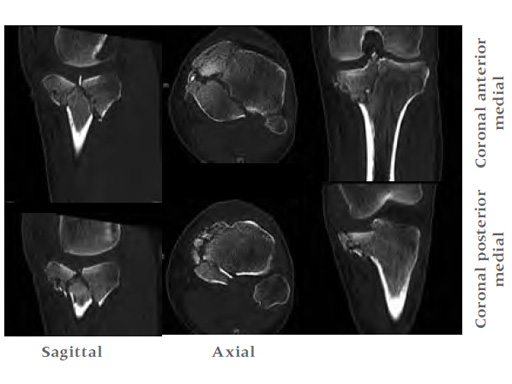

A 33-year-old male was involved in an altercation and suffered a gun shoot wound to his knee

Initially taken for incision and drainage and then ORIF . Patient placed in a floppy lateral position with the effected lower extremity externally rotated (opposite hip and shoulder bumped up about 3040) allowing exposure of the posterior medial knee. A posterior medial and an anteromedial incision were used to repair the fracture with a 67 cm skin bridge.